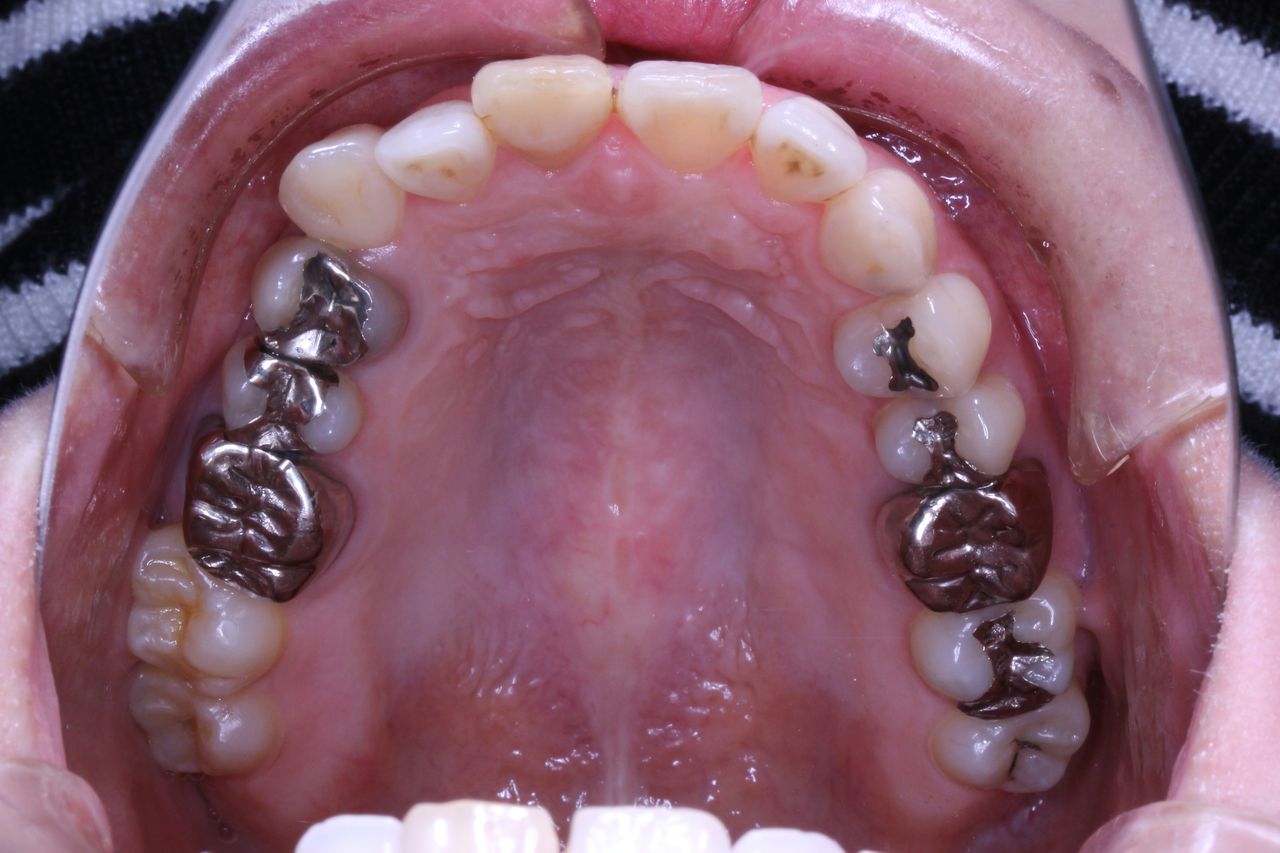

治療開始から3年経過した現在の状況です

もともとは

上の歯列はどうでしょうか?